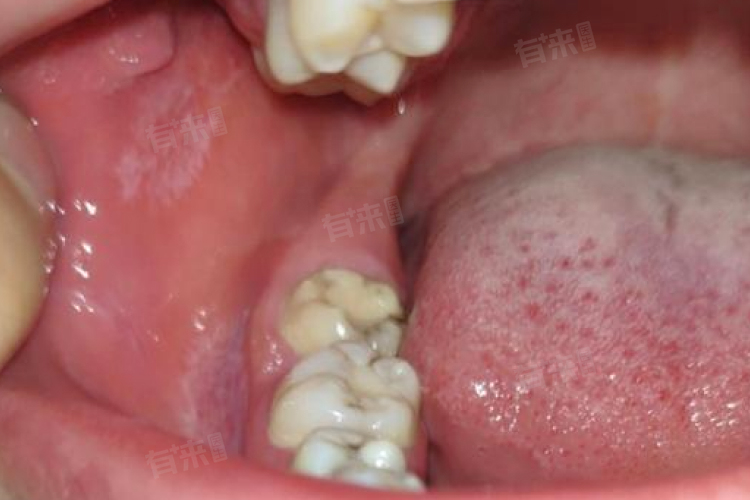

2、口腔黏膜质地改变:患者会感觉到口腔黏膜变硬、弹性降低,触摸时能明显感觉到黏膜变得粗糙,有时还会出现小硬结。例如,在触摸颊黏膜时,会发现原本柔软的黏膜变得像皮革一样硬韧。

3、口腔功能受限:由于口腔黏膜纤维化,患者在张口、吞咽、说话等方面会受到不同程度的影响。张口度会逐渐变小,严重时甚至只能张开1-2厘米,影响进食和口腔清洁;吞咽时可能会有异物感、疼痛感,尤其是在吞咽较硬或刺激性食物时更为明显;说话时可能会因为口腔肌肉运动受限而发音不清。